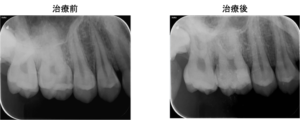

今回は、右上奥歯の大きな虫歯に対して、神経の保存を行った症例をご紹介致します。

右上6番に大きな虫歯があり、虫歯の範囲が歯の中の神経に近接していました。通常の保険診療では歯の神経を抜く治療(歯の根の治療)になりますが、電気的な検査で神経の反応は正常であったので、虫歯治療と神経の保存療法(歯髄保存療法)を提案し、患者様の合意を頂いたので治療をすすめることになりました。

上のレントゲン写真では右上6番に虫歯で歯が溶けている部分があります(矢印部) 。

治療後